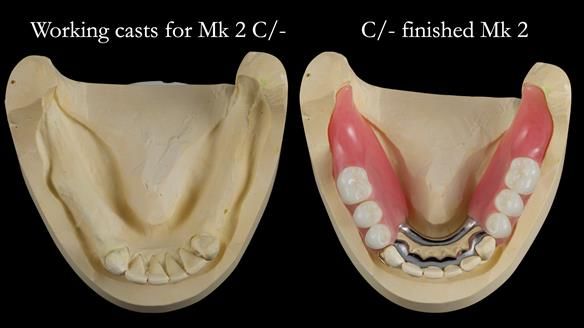

This newsletter describes the full protocol workflow of a complete upper denture and a lower partial denture for Jo.

- The lower front teeth (LR3 – LL3) have better prognosis (although, I think there is high chance of loss – over the next 10 - 15 years). However, I do not believe it is right to remove them as they are in good condition compared with the other teeth and coping with a lower full denture is far more difficult (affecting your quality of life) than a lower metal based partial denture supported by natural teeth as proposed in the treatment plan below.

- The forces placed on the teeth are large (bruxism). This will make the dentures proposed in the treatment plan below wear, chip and break more quickly. Therefore, the final dentures will require metal reinforcement to make them as robust as possible.

The clinical situation and treatment process is shown in detail below. I provided the clinical work. Rowan Garstang provided the technical work. This treatment took 25 visits over a period of 12 months.